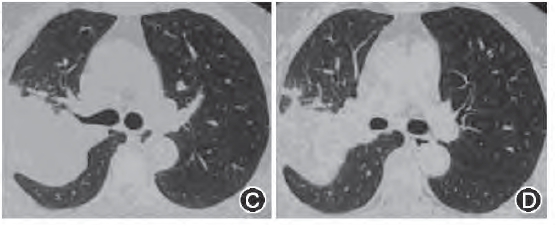

入院查血常规无异常,ESR为57 mm/1 h,T—SPOT (SFCs/106 PBMC):A 15,B 11,PPD试验(++),痰培养:抗酸杆菌及真菌均为阴性,自身免疫病相关检查指标阴性,复查支气管镜:右B1支气管闭塞,右B2支气管狭窄,右上叶支气管开口色素沉着,右B1及B2支气管冲洗液:抗酸染色、瘤细胞、细菌培养未见明显异常,右B2支气管冲洗液真菌培养示白色念珠菌。右B1及B2黏膜活检病理报告:支气管非坏死性肉芽肿性炎,病原体染色阴性。胸部CT示右上叶尖段斑片结节影伴有空洞形成,右上叶后段大片实变影(图3)。拟诊肺结核,诊断性抗结核治疗(HRZE),1个月后复查x线胸片示右肺病变较前吸收好转。

图3 胸部CT示右上叶尖段斑片结节影伴有空洞形成,右上叶后段大片实变影

谢汝明:该患者胸部CT示右上叶尖段斑片结节影伴有空洞形成,右上叶后段肺实变影,从影像表现首先考虑肺结核,结合穿刺物病理结果为肉芽组织,肺结核诊断成立。